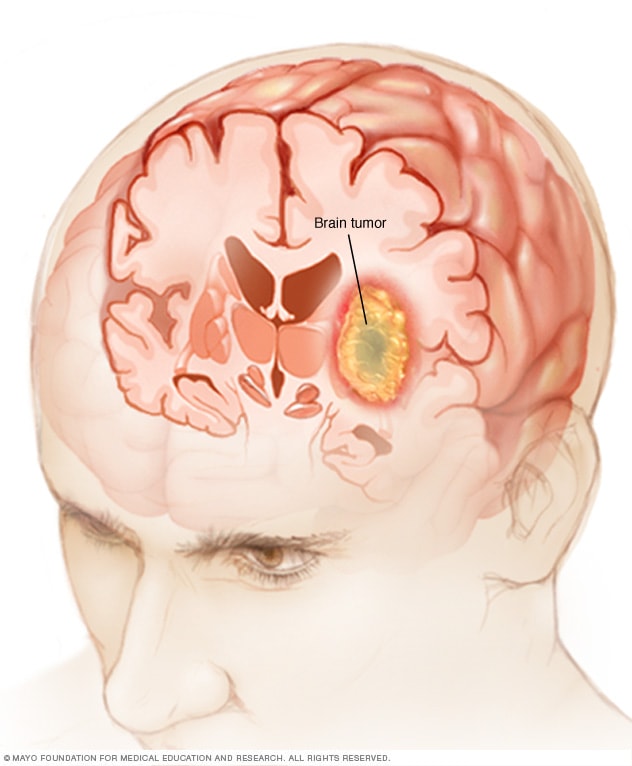

A brain tumor can form in the brain cells (as shown), or it can begin elsewhere and spread to the brain. As the tumor grows, it creates pressure on and changes the function of surrounding brain tissue, which causes signs and symptoms such as headaches, nausea and balance problems.

A brain tumor is a growth of cells in the brain or near it. Brain tumors can happen in the brain tissue. Brain tumors also can happen near the brain tissue. Nearby locations include nerves, the pituitary gland, the pineal gland, and the membranes that cover the surface of the brain.

Brain tumors can begin in the brain. These are called primary brain tumors. Sometimes, cancer spreads to the brain from other parts of the body. These tumors are secondary brain tumors, also called metastatic brain tumors.

Many different types of primary brain tumors exist. Some brain tumors aren't cancerous. These are called noncancerous brain tumors or benign brain tumors. Noncancerous brain tumors may grow over time and press on the brain tissue. Other brain tumors are brain cancers, also called malignant brain tumors. Brain cancers may grow quickly. The cancer cells can invade and destroy the brain tissue.

Brain tumors range in size from very small to very large. Some brain tumors are found when they are very small because they cause symptoms that you notice right away. Other brain tumors grow very large before they're found. Some parts of the brain are less active than others. If a brain tumor starts in a part of the brain that's less active, it might not cause symptoms right away. The brain tumor size could become quite large before the tumor is detected.

Brain tumor treatment options depend on the type of brain tumor you have, as well as its size and location. Common treatments include surgery and radiation therapy.